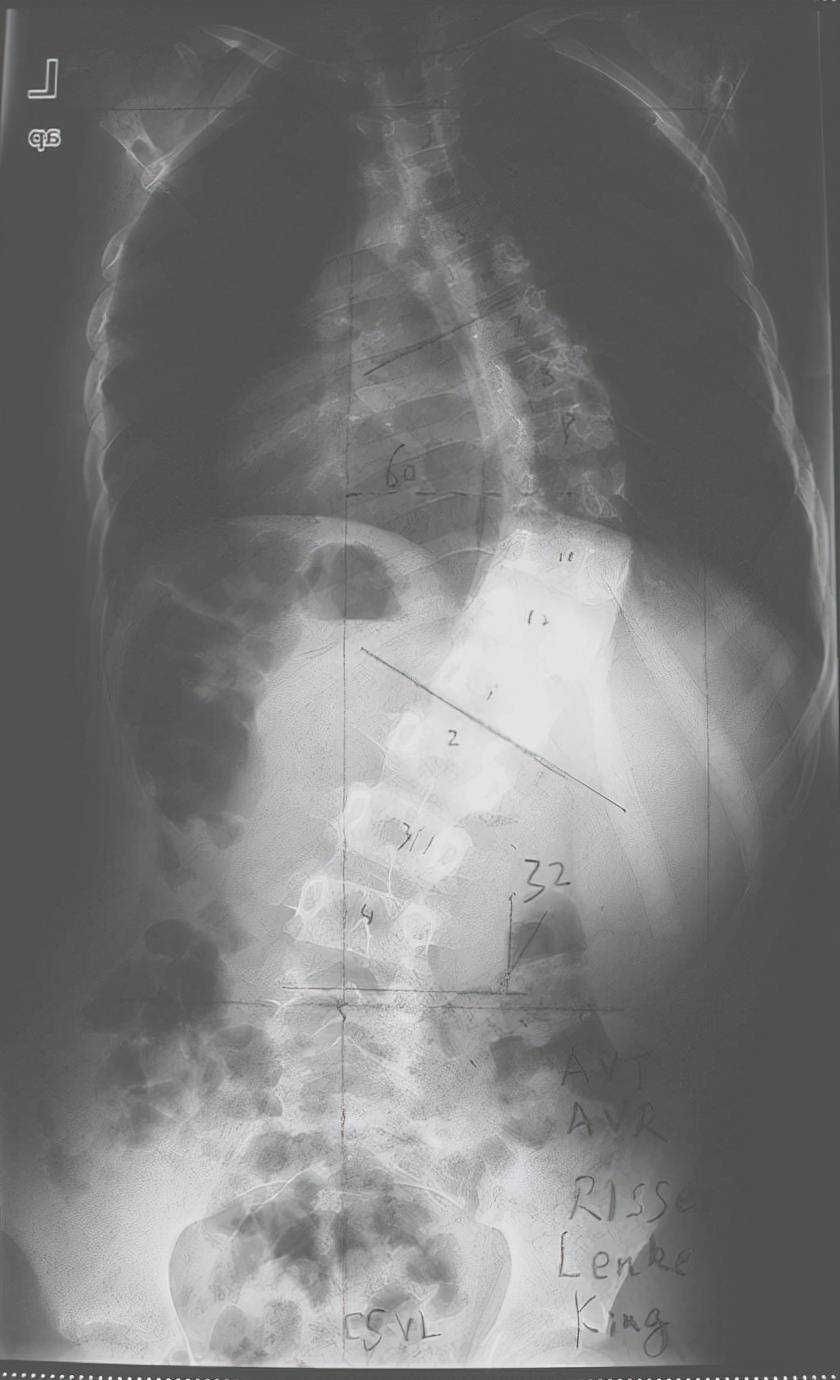

经过检查后,考虑患儿为脊柱侧弯,x光片显示为轻度侧弯,经过测量,侧弯

脊柱侧弯是一种复杂的三维脊柱畸形,按照年龄阶段又可以划分为:婴儿型

「婴儿型特发性脊柱侧弯」相当罕见,且多会自己恢复正常,只有少部人